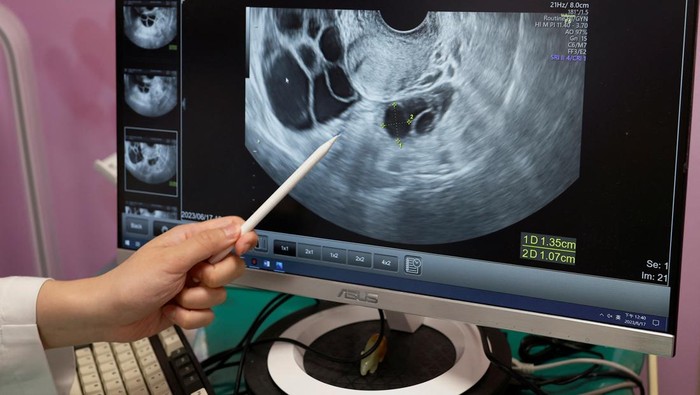

Namun, ada sesuatu yang menarik di Taiwan. Berbarengan dengan anjloknya angka kelahiran, kini wanita lajang di sana justru beramai-ramai menginginkan prosedur pembekuan sel telur (egg freezing). Dengan harapan, suatu hari mereka bisa memiliki anak.

Sebuah studi di Rumah Sakit Universitas Nasional Taiwan mengungkapkan, jumlah wanita berusia 35 hingga 39 tahun yang melakukan pembekuan sel telur meningkat hingga 86 persen dalam tiga tahun terakhir.

Sebelum menjalani operasi, Tung rutin mengunjungi rumah sakit setiap dua sampai tiga hari untuk tes darah. Ia menjalani pemeriksaan kadar hormon untuk melihat bagaimana sel telur berkembang, seringkali pada waktu yang tidak teratur seperti jam 9 malam karena jadwal kerjanya.